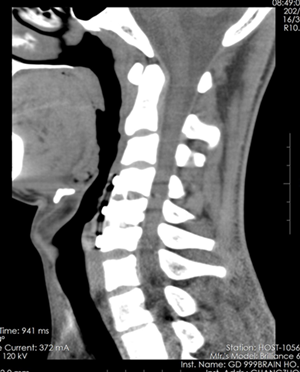

患者,张XX,男性,15岁,因“颈部外伤后四肢不全瘫近10个月”收入院。患者于2018年01月自高处跌落致颈部外伤,伤后昏迷,苏醒后发现四肢不能活动,急送当地医院行颈椎MRI检查示“颈5、6椎体骨折,颈5后脱位,颈4-6脊髓损伤”,行牵引治疗后于2018年01月26日在当地医院行“颈椎前路颈4-6椎管减压椎间植骨融合内固定术”,术后加强营养神经及数月的康复治疗,双下肢力量有所改善,扶持助行器可行走一段距离,但是双下肢肌张力增高明显,下肢外展困难,双足下垂,肢体协调性差,易跌倒。遂于2018年11月22日来我院就医。

术前

术后